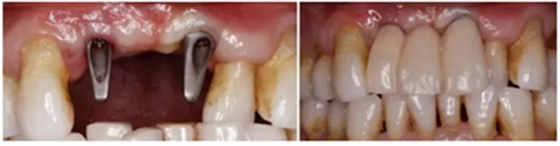

(2)數(shù)字化3D種植外科導(dǎo)板的設(shè)計(jì)制作

4.png

(3)數(shù)字化3D種植外科導(dǎo)板引導(dǎo)下Straumann 3.3x12 NC 種植體行延期種植

5.png